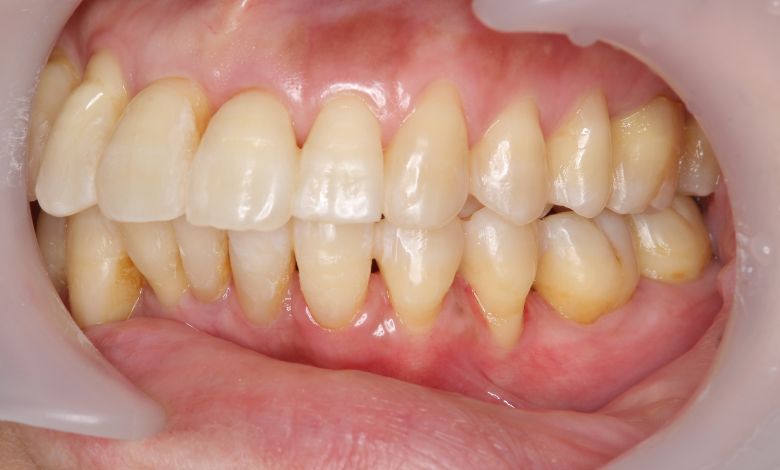

叢生が解消され、歯列全体にわたり滑らかで調和のとれた配列が得られています

上下の前歯の重なりが解消され、歯軸の傾きも整いました。咬合関係も安定しています

歯列弓はV字型から自然でゆったりとしたU字型へと広がり、唇側に転位していた犬歯も正しい歯列内に整列されています。

上下の前歯の重なりや段差は完全に解消され、咬合関係も安定してる。自然なスマイルラインが形成され、口元の印象も大きく改善された